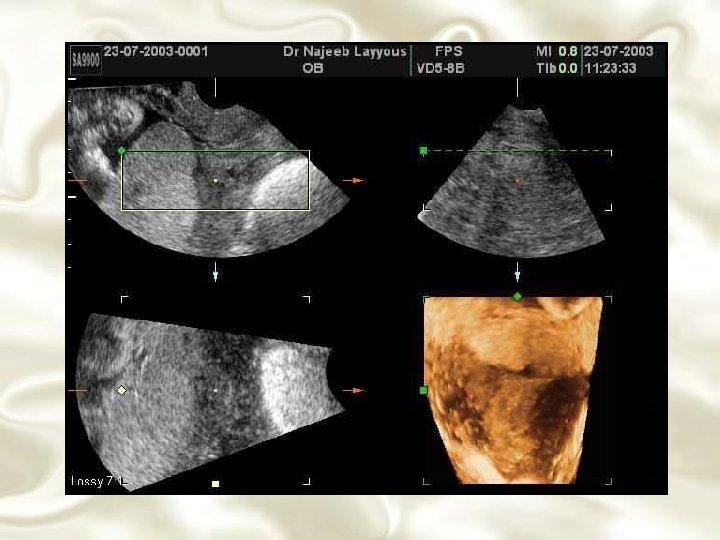

DIAGNÓSTICO LABORATORIAL • Exame hematológico • Pesquisa de hemáceas fetais • Localização da placenta – Métodos radiológicos – Rx, angiografia, arteriografia, amniografia, cistografia, proctografia • Migração placentária

Placenta Prévia Identificação ultra-sonográfica de placenta prévia e doença clínica subsequente